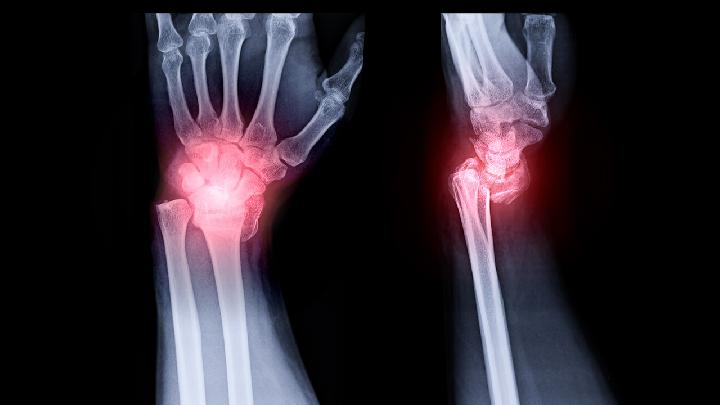

骨髓炎是指化脓性细菌感染骨髓、骨皮质和骨膜而引起的炎症,以感染骨膜下脓肿、骨质破坏、死骨形成、反复炎症刺激引起骨膜增生、局部肿大为特点,是比较常见的且难治愈的疾病之一,很多患者都害怕被传染,那么,得了颈椎骨髓炎会传染么?

骨髓炎是一种日常生活中比较常见的疾病,相信大家对它并不陌生,骨髓炎的发生对骨骼的破坏和感染都比较严重,对患者的身体危害也很大,可能会导致化脓性关节炎,骨骼畸形或者肢体生长障碍等,那么,对骨髓炎的中医诊断方法有哪些呢?